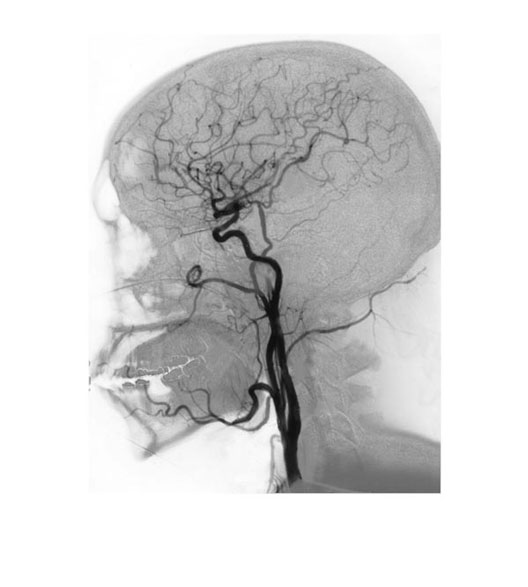

Head Angiogram

1. Common Carotid Artery

2. Internal Carotid Artery

3. Ascending Pharyngeal Artery

4. Occipital Artery

5. Superficial Temporal Artery

6. Middle Cerebral Artery

7. Anterior Cerebral Artery

8. Middle Meningeal Artery

9. Maxillary Artery

10. Facial Artery

11. Lingual Artery

12. External Carotid Artery

13. Superior Thyroid Artery